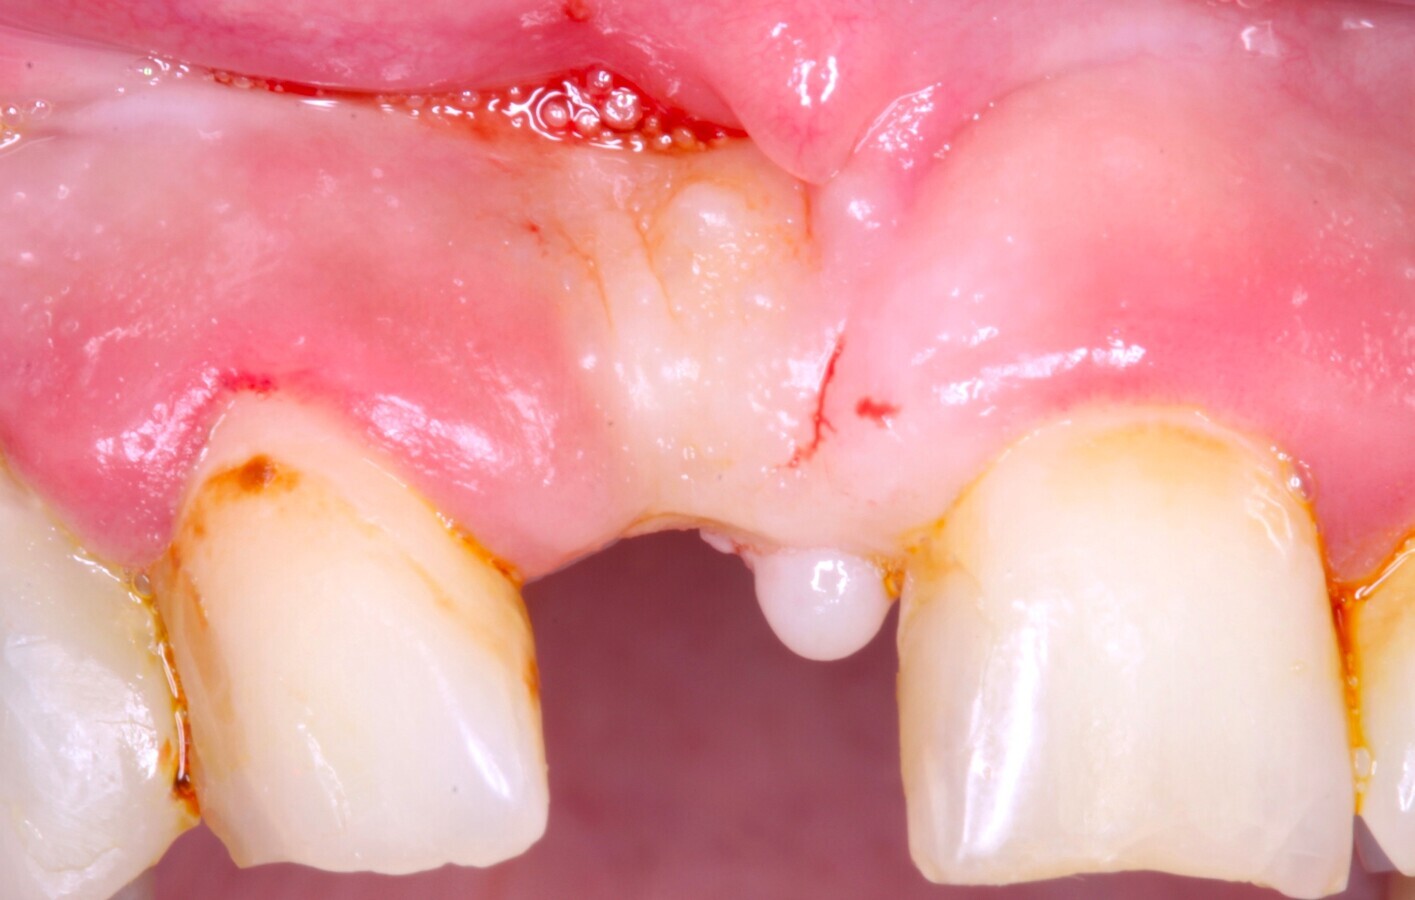

LECHO RECEPTOR

Fig. 15 Figura 15

5. Fijación del injerto previamente modelado al lecho con microtornillo de 1.5 a 2 mm de diámetro.

Fig. 16 Figura 16

6. Relleno de hueso particulado en la intersección entre el injerto óseo y el lecho receptor.

Fig. 17 Figura 17

7. Recubrimiento con una membrana reabsorbible o no reabsorbible para evitar la infiltración de tejido blando y garantizar la regeneración del defecto.

8. Fijación de la membrana con chinchetas para evitar su desplazamiento durante la reposición del colgajo.